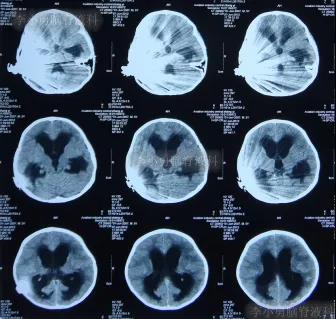

2012年8月15日(外院人工耳蜗植入术后近4个月时间内:经3家三甲医院治疗后但脑积水和颅内感染仍持续加重,但李小勇脑脊液科治69天康复出院);出院时:病情好转为:开始恢复走路能力,面瘫消失(图-13);脑CT示未见异常,人工耳蜗被保留(图-14)。

图-13:2012年8月15日

图-14:2012年8月15日脑CT